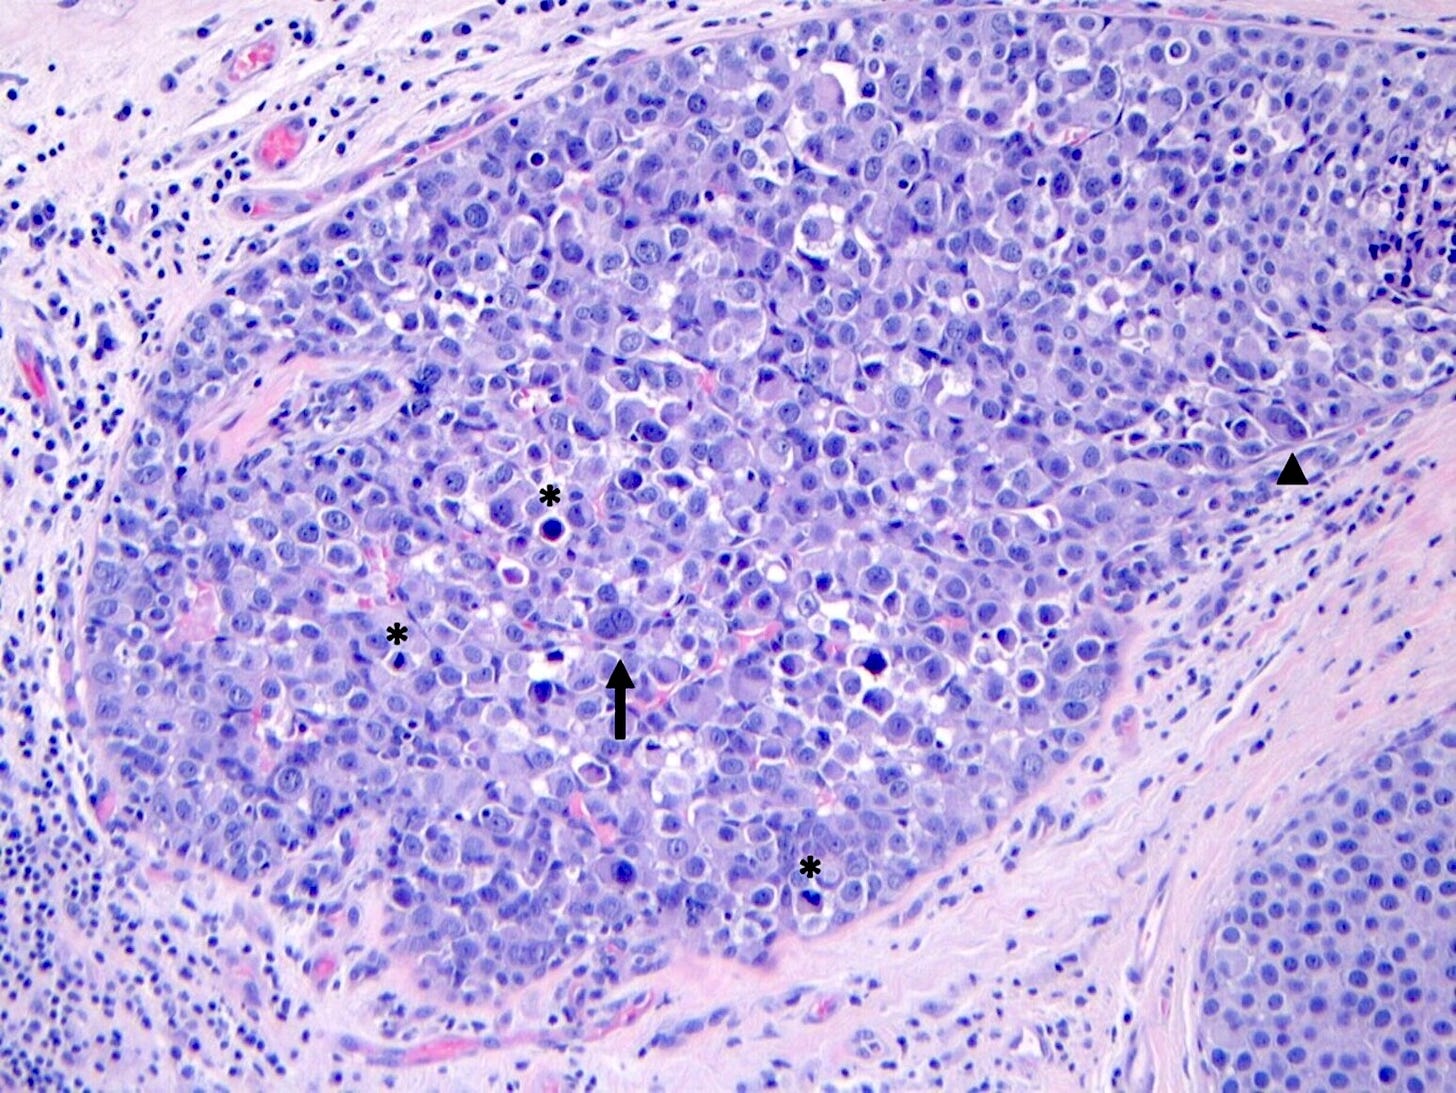

Pleomorphic lobular carcinoma in situ - microscopic images

Pleomorphic LCIS is a rare (< 5% of LCIS) nonclassical or variant form of lobular carcinoma in situ composed of a noninvasive, neoplastic proliferation of large dyscohesive cells with marked nuclear pleomorphism. Its nuclei are > 4 times the size of a lymphocyte and its cytologic features more closely resemble high grade DCIS than classic LCIS. It may exhibit comedonecrosis and calcifications. However, other features overlap with classic LCIS: loss or dysfunction of E-cadherin, cellular dyscohesion, lack of cell polarity, intracytoplasmic lumina, signet ring cells and pagetoid spread. Most cases are associated with classic LCIS and ALH.

Immunostains for E-cadherin may assist in distinguishing LCIS from DCIS although they must be interpreted in the context of the histologic features.

Pleomorphic LCIS accumulates additional alterations and generally exhibits greater genomic instability than classic LCIS.

Pleomorphic LCIS has features of a high risk precursor lesion of invasive carcinoma. It is associated with a high incidence (49%) of associated invasive carcinoma either on core needle biopsy or excision. Treatment consists of surgical excision but there is no consensus on requiring negative margins, adjuvant treatments or sentinel node biopsy.